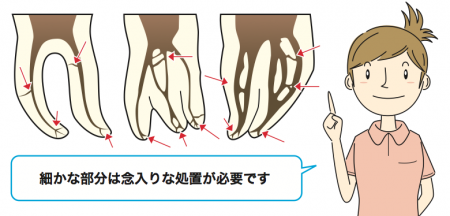

神経の管は人それぞれ複雑な構造になっているため念入りな処置が必要になります

抜髄処置の場合は、根管の清掃と洗浄は予定では2回行います。

痛みや違和感が消失しない場合は根管治療を繰り返します。

根管治療が進むと根管に密閉し感染の再発を

防ぐために特殊な充填材を詰めます